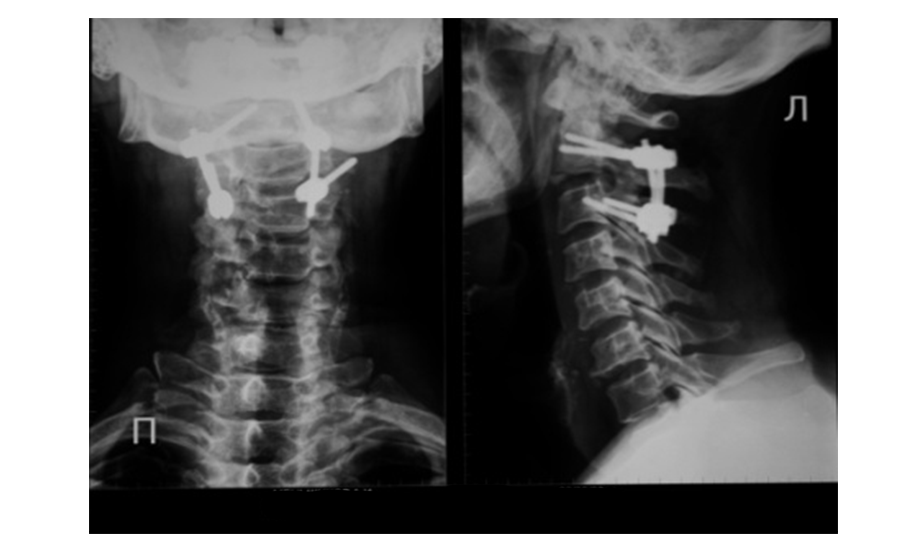

Рис.2 Произведена репозиция и фиксация перелома палача. Смещение устранено. Ножки позвонка соединены транспедикулярными винтами